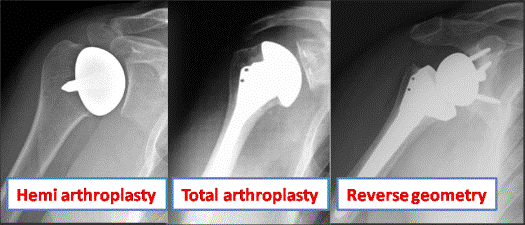

Joint Replacement also known as an arthroplasty (see video -Total shoulder replacement) The shoulder replacement is an artificial joint which is made of metal and plastic. Arthritis affects every patient differently and there are several different types of joint replacement. The correct choice of implant is essential for a good outcome and you should discuss this with your surgeon.

The hemi arthroplasty- The surface of the joint is replaced with a smooth metal head and the other side of the joint is left alone. This is the least invasive option and is the most commonly performed arthroplasty.

The total shoulder replacement- if the cartilage and bone on the socket (glenoid) side of the joint is also badly worn; a plastic polyethylene tray is used to resurface it and this articulates with the metal head. It gives a better range of movement than the hemi arthroplasty but over 10-20 years the plastic wears away and complex revision may become necessary.

The Reverse geometry- the above operations require good muscle function around the shoulder to work properly. In some patients the muscles of the rotator cuff are damaged; if this is the case a reverse geometry shoulder replacement can restore excellent function in what would otherwise be a useless, painful shoulder.